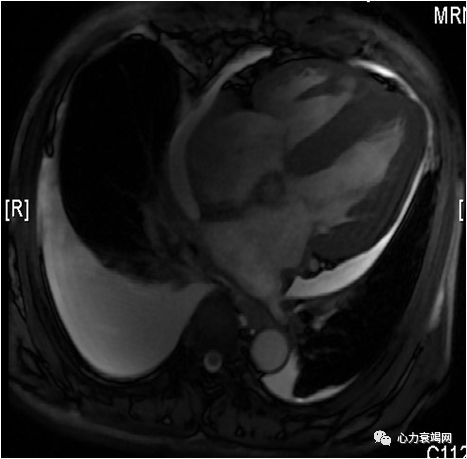

➤ 心脏MRI:检查过程中患者心律不齐,心率87次/分 双房增大(左房前后径:44mm,右房径前后径×左右径55×56mm)。两心室腔内径较小(左室舒张期短轴横径约40mm,右室横径约28mm)。左室各节段室壁普遍增厚(室间隔最厚约20mm,侧壁11mm,心尖部10mm);右室壁亦增厚,厚度约8mm。双室心尖部形态正常,未见闭塞,右室流出道不宽。两心室收缩功能减低,舒张运动受限,舒张期未见室间隔抖动征象。左室流出道通畅。 二尖瓣、三尖瓣可见少量返流信号,主动脉瓣未见返流信号。心包腔内少量积液信号。

➤ 心功能检查:LVEF 30%,CO 2.8 L/min,左室舒张末容积约 109 ml,EDVi 59.0 ml/m?。 右侧中量胸腔积液,左侧少量胸腔积液。

➤ 心脏MRI:双室壁增厚伴心功能减低,考虑心肌受累疾患,建议对比剂增强扫描,进一步明确心肌的组织学特性; 少量心包积液;右侧中量胸腔积液,左侧少量胸腔积液。